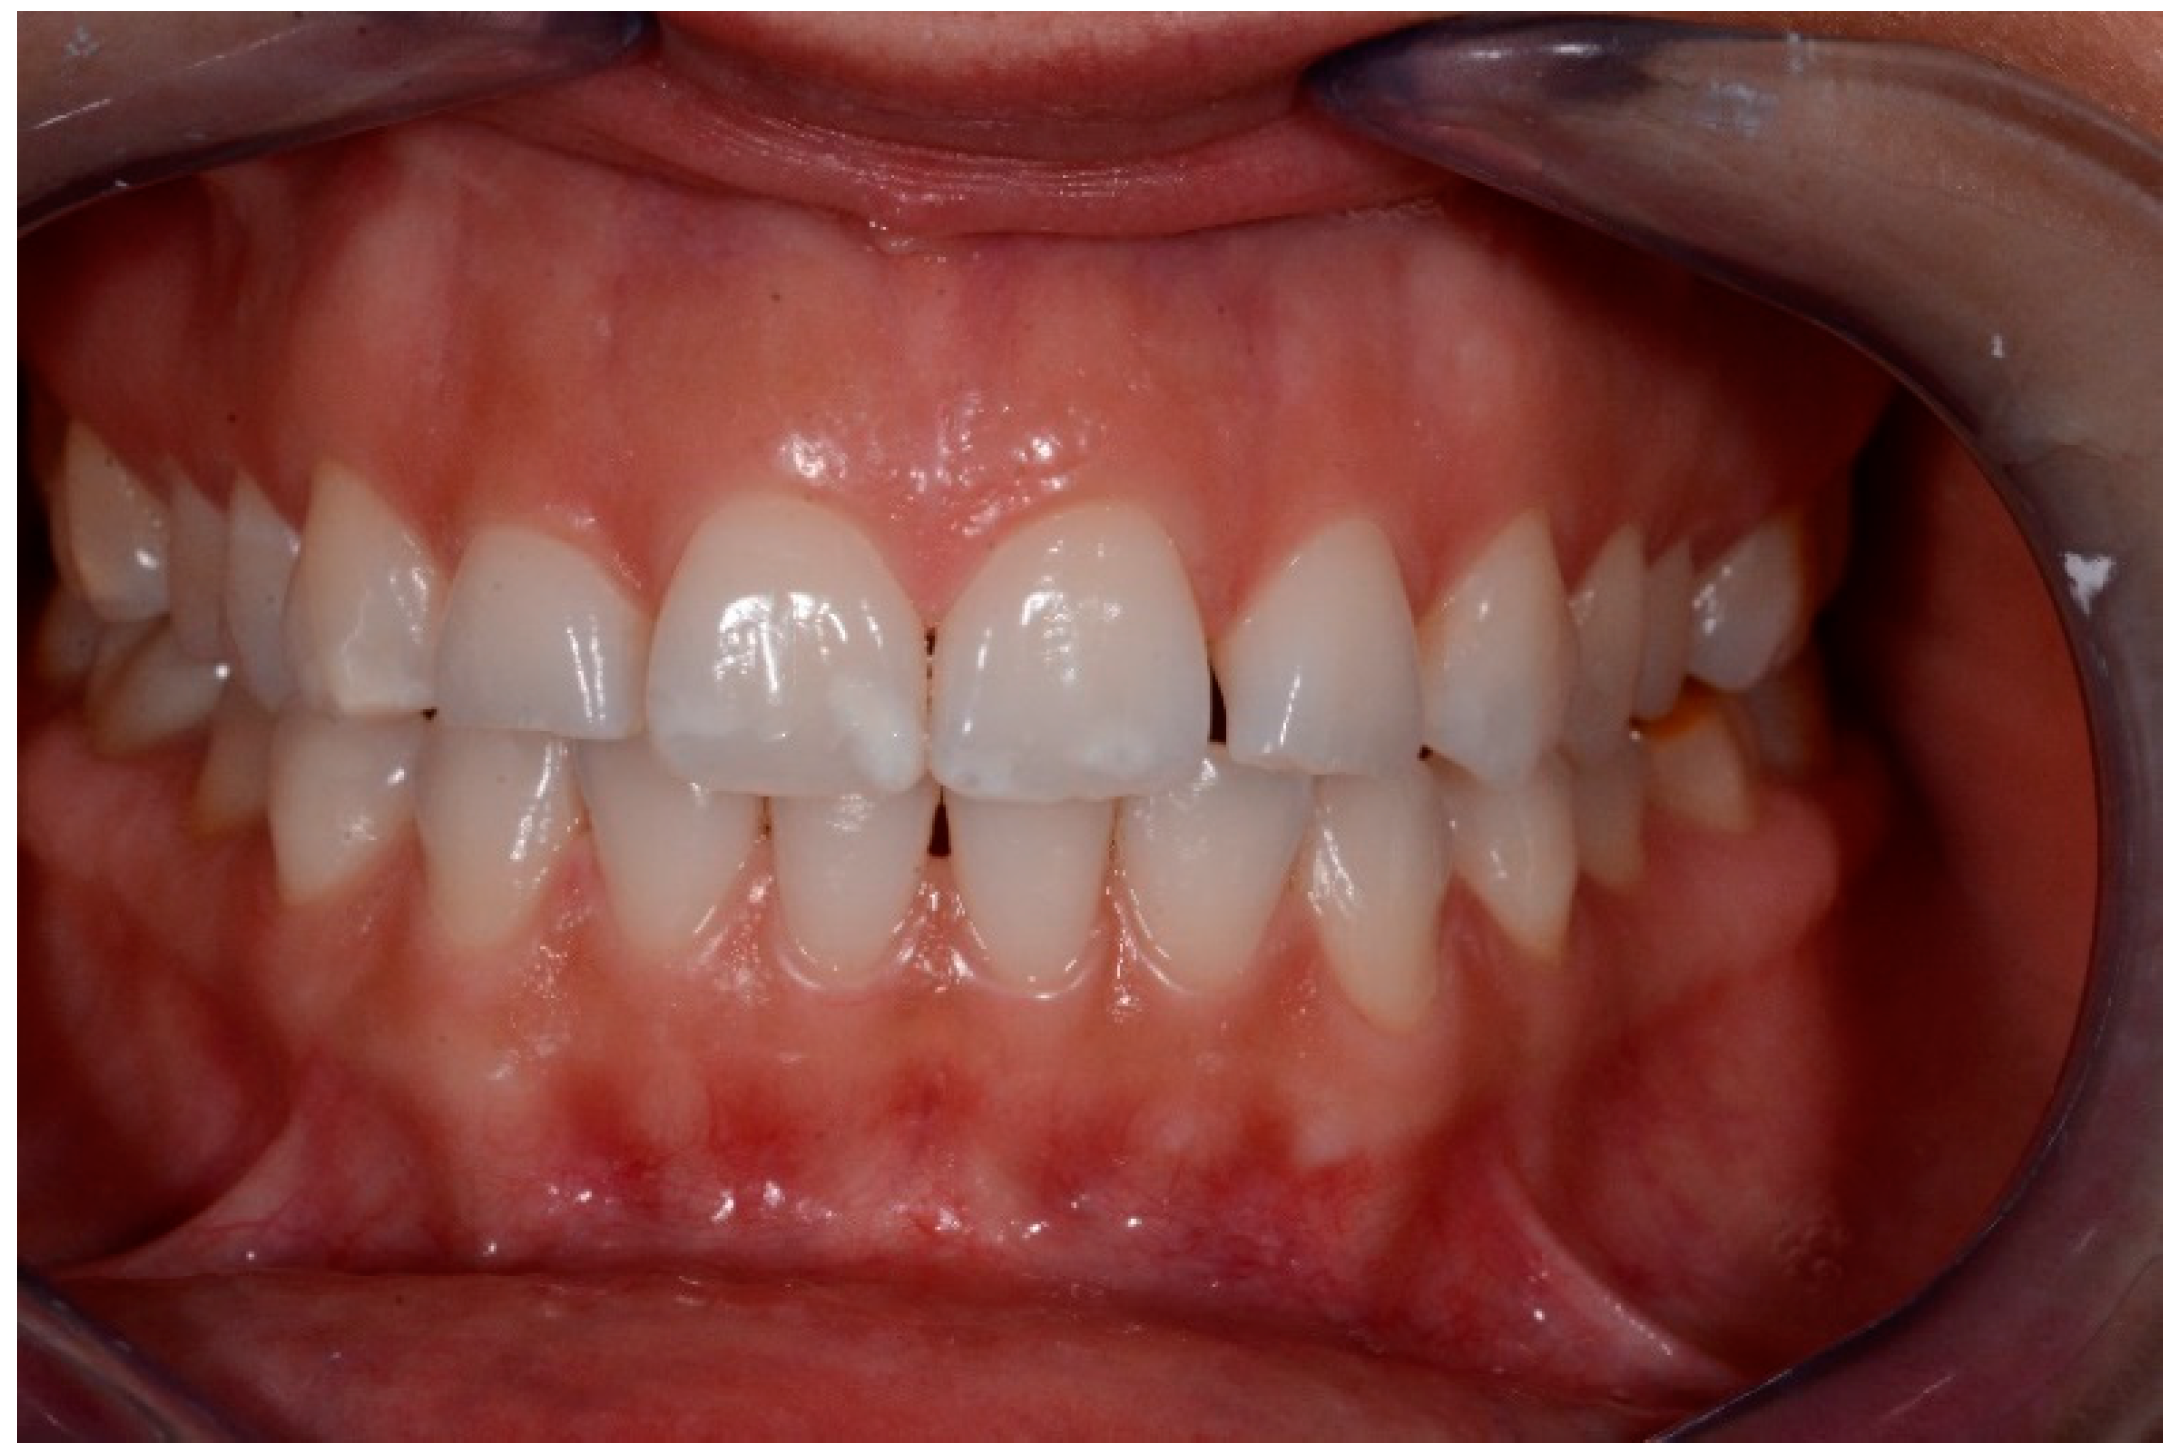

- polishing of surfaces, check of contact points and finishing with abrasive stripes in interproximal areas requiring. (Figure 3)